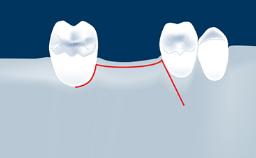

- intraoperative complications of lateral window sinus floor elevation